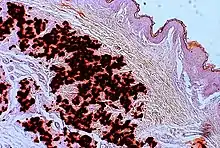

The diagnostic criteria for PXE are the typical skin biopsy appearance and the presence of angioid streaks in the retina. Criteria were established by consensus of clinicians and researchers at the 2010 biennial research meeting of the PXE Research Consortium.[29] and confirmed at the 2014 meeting[30] These consensus criteria state that definitive PXE is characterized by two pathogenic mutations in the ABCC6 or ocular findings – angioid streaks > 1 DD or peau d’orange in an individual <20 years of age together with skin findings:

- Characteristic pseudoxanthomatous papules and plaques on the neck or flexural creases.

- Diagnostic histopathological changes in lesional skin: Calcified elastic fibers in the mid and lower dermis, confirmed by positive calcium stain

| Pseudoxanthoma elasticum | LM: Mid-dermal calcification and fragmentation of elastic fibers EM: Mineralization in elastic fiber core |